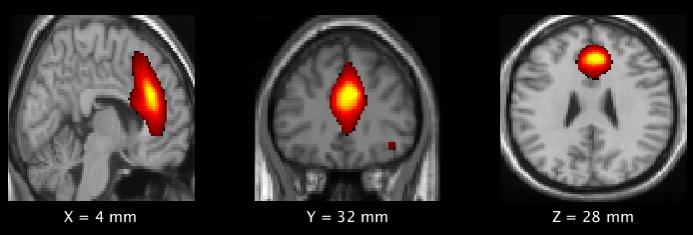

Pre- and post-season resting state functional (fMRI) scans were performed on all players, and changes in power within five components the default mode network (DMN) were analyzed.

The DMN is a network of regions deep in the gray matter areas of the brain. It includes structures that activate when a person is awake and engaging in introspection or processing emotions, which are activities that are important for brain health.

The post-season results showed significant increases in power and gray matter volume in the frontal DMN in the high-impact group.

"Disruption in normal pruning has been shown to be related to weaker connections between different parts of the brain," Murugesan said. "Our study has found a significant decrease in gray matter pruning in the frontal default mode network, which is involved in higher cognitive functions, such as the planning and controlling of social behaviors."